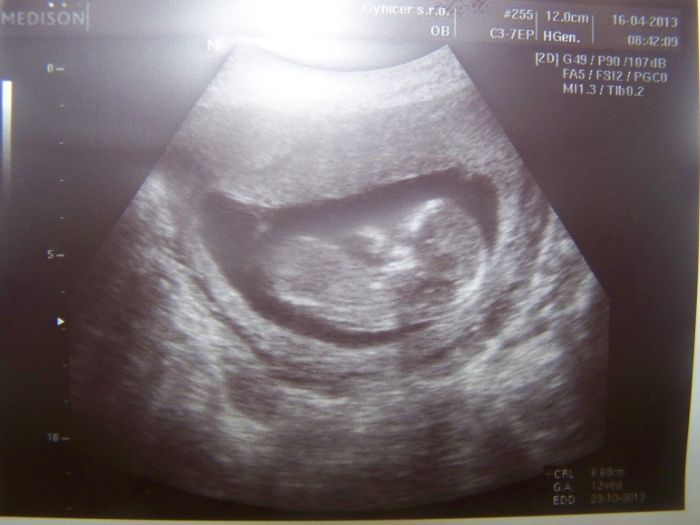

tak se hlásím po delší době. Zkoukla jsem fotečky UTZ, bříšek i kočárků.

Jsem právě 16tt, bříšenko pomaličku roste, nevolnosti pomalu vymizely, zato mě chytají ty pravé těhu chutě :-) Na váhu raději nejdu, abych se nevyděsila, haha. Ale naposled jsem měla 76kg, na poradnu a UTZ jdu 9.5. tak jsem zvědavá, zda mi u řekne, kdopak se nám to v bříšku schovává. Jinak už jsem taky neodolala a máme náš vysněný kočárek doma :-) s nákupem věciček čekám, máme toho dost po Matyáškovi, jsou tam i neutrální věcičky, no a kdyby to byla slečna, tak mám dodavatelku kamarádku, jejíž holčička bude mít v době narození našeho miminka právě roček.

Dám vám sem fotečky UTZ a kočárku a ve čtvrtek napíšu novinky z poradny.